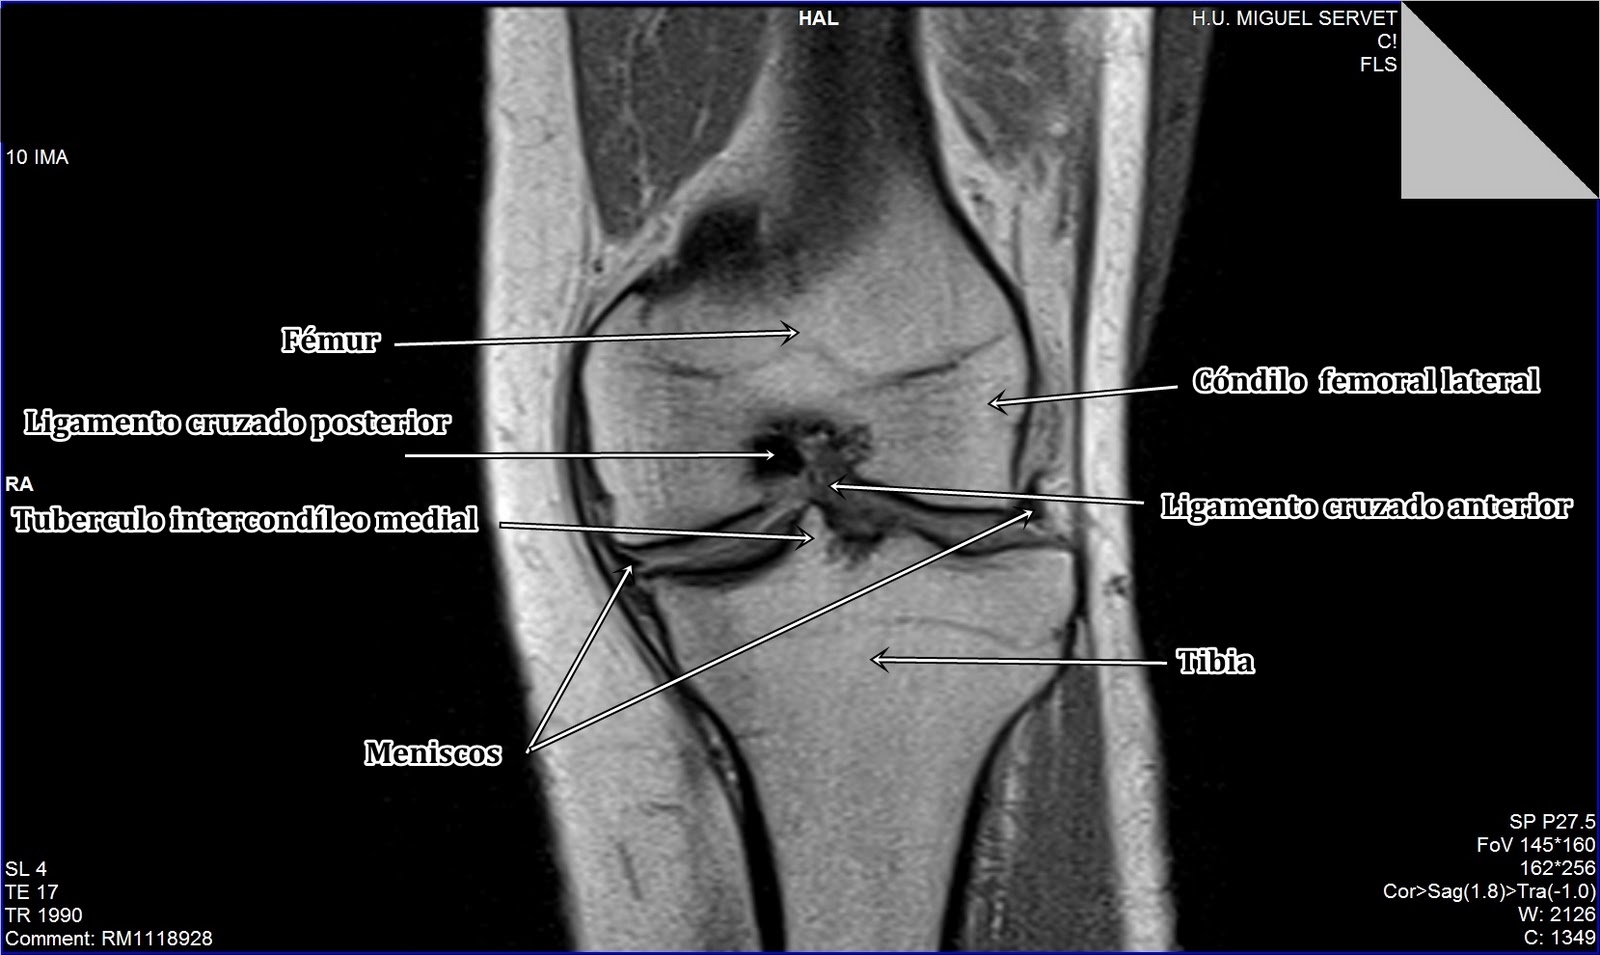

WebEn concreto, para una resonancia magnética de la rodilla, es probable que entre con los pies por enfrente y, por lo general, puede esperar que la mitad inferior de. WebPara una resonancia magnética de la rodilla, entrará con los pies por enfrente y solo la parte de abajo del cuerpo estará en el tubo. Es de aguardar que permanezca inmóvil. Webun ensayo argumentativo sobre el uso de los pirotécnicos; ministra de la mujer y poblaciones vulnerables 2022; alineamiento y balanceo surco; arquitectura colonial de. Web𝐑𝐞𝐬𝐨𝐧𝐚𝐧𝐜𝐢𝐚 𝐦𝐚𝐠𝐧é𝐭𝐢𝐜𝐚 𝐝𝐞 𝐫𝐨𝐝𝐢𝐥𝐥𝐚 𝐞𝐧 𝐌𝐚𝐝𝐫𝐢𝐝Sabemos que cuando necesitas algún tipo de ... Webresonancia rodilla te meten enteradr salcedo gastroenterólogo ica deca durabolin resultados WebLa resonancia magnética de la rodilla utiliza la energía de potentes imanes para crear imágenes de la articulación de la rodilla y de los músculos y tejidos. Las.